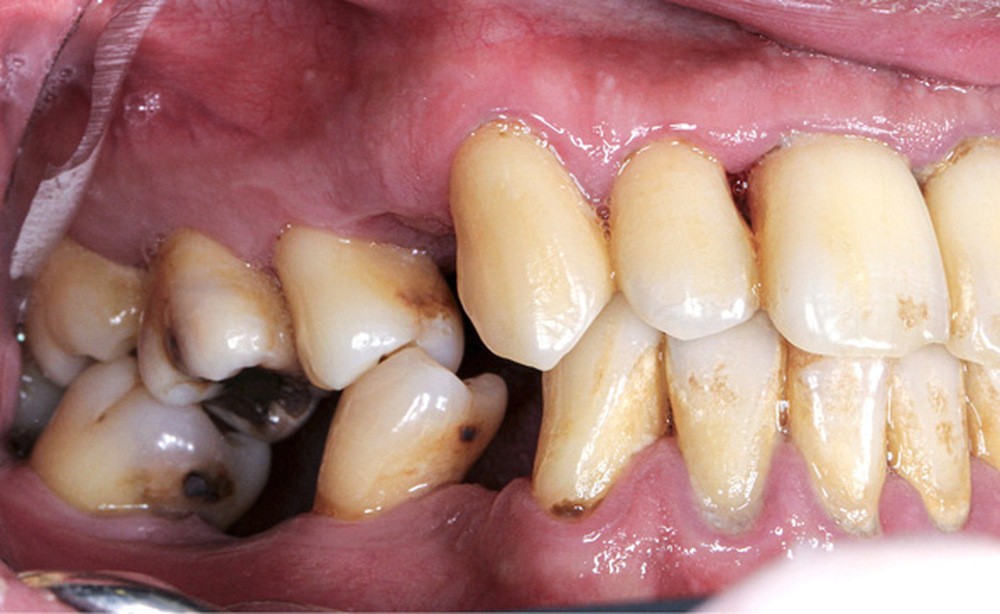

L’obésité, définie par un indice de masse corporelle (IMC) ≥ 30 kg/m2, est une maladie inflammatoire chronique complexe et multifactorielle caractérisée par un dépôt excessif de graisse dans le tissu adipeux. Selon l’OMS, depuis 1975, le nombre de cas d’obésité a presque triplé à l’échelle planétaire [1]. En 2020, près d’un Français sur deux était en surpoids, tandis que 17 % étaient obèses [2]. Or l’obésité est responsable d’une haute mortalité à l’échelle mondiale et est un facteur de risque majeur pour de nombreuses maladies, dont les maladies cardiovasculaires, le diabète de type 2 et certains cancers [1]. Son impact sur la santé des populations et son coût économique et social sont donc considérables. Ces deux dernières décennies, de nombreuses études ont montré que l’obésité pouvait aussi être incriminée dans la détérioration de la santé bucco-dentaire [3] (fig. 1 à 7).